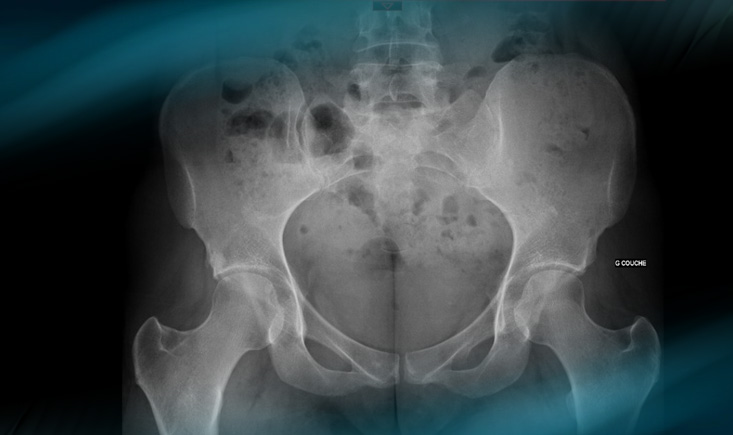

Standard - X-rays

Standard – x-rays

• ✔️ Femoro acetabular impingement Pincer type By TRUE acetabular retroversion (acetabular posterior dysplasia)

3 signs: cross-over sign, ischial spine sign, posterior wall sign

Retroversion index > 30%

Femoro acetabular impingement Pincer type By TRUE acetabular retroversion